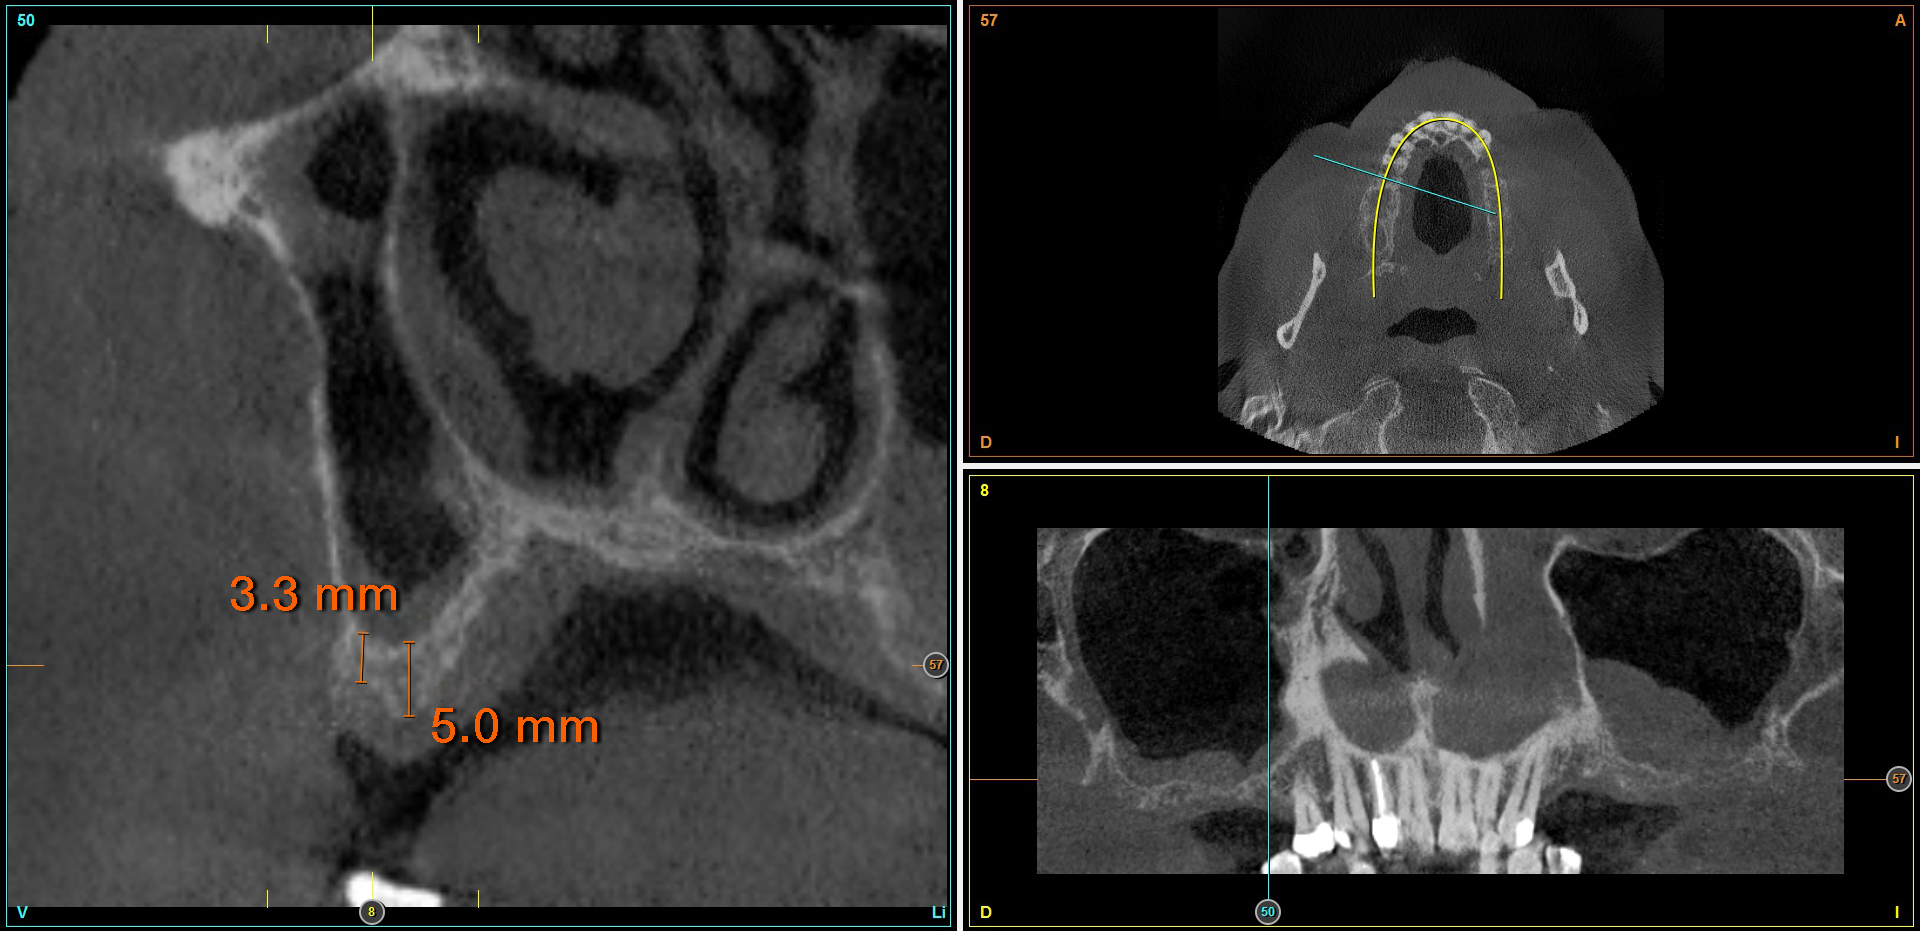

È stata effettuata una revisione retrospettiva di tutti i casi nei quali sono stati inseriti impianti di 4,5 mm di lunghezza sottoposti a protocollo di carico immediato. I trattamenti sono stati eseguiti in un’unica clinica di Vitoria (Spagna) negli anni 2020 e 2021. Nell’ambito dello studio preoperatorio, tutti i pazienti sono stati valutati mediante esame clinico, modelli diagnostici e CBCT (Cone Beam), successivamente analizzati con un software di pianificazione dedicato (BTI-Scan III). Al fine di definire con precisione la futura riabilitazione, è stato eseguito un ceraggio diagnostico dal quale è stata realizzata una guida chirurgica personalizzata.

L’altezza media della cresta ossea residua era di 5,11 ± 1,06 mm, mentre la densità ossea media nelle sedi implantari era di 566,67 ± 349,48 HU. Il torque medio di inserimento degli impianti è stato di 34,71 ± 18,25 Ncm. L’analisi del torque in funzione della posizione implantare e del tipo di osso ha evidenziato un comportamento biomeccanico coerente con la densità ossea attesa per ciascuna regione anatomica. Gli impianti inseriti in osso di tipo I e II hanno generalmente raggiunto valori di torque più elevati, frequentemente compresi tra 40 e 60 Ncm, soprattutto nelle regioni posteriori (26, 27, 36 e 37). Al contrario, negli impianti inseriti in osso di tipo III e IV, i valori di torque tendevano a essere inferiori e più dispersi, oscillando prevalentemente tra 20 e 40 Ncm. Nonostante ciò, anche nei siti con qualità ossea inferiore, i valori ottenuti rientravano in intervalli clinicamente accettabili per consentire la stabilità primaria necessaria ai protocolli di carico immediato adottati nello studio. Nel Grafico 3 è riportata la distribuzione del torque in base alla sede anatomica e al tipo di osso.

In 19 impianti sono state eseguite procedure complementari contestualmente all’inserimento implantare: in due casi rigenerazione verticale con osso autologo da fresaggio associato a PRGF-Endoret; in 11 casi rialzo del seno mascellare transalveolare con osso autologo e PRGF-Endoret; in sei casi sovracorrezione vestibolare mediante osso autologo e PRGF-Endoret, associando uno strato di biomateriale (idrossiapatite bovina) per ridurre il riassorbimento volumetrico. Quattro impianti da 4,5 mm sono stati ferulizzati ad altri impianti della stessa lunghezza, per un totale di otto impianti ultra-corti ferulizzati tra loro, configurando ponti supportati da tre impianti. La protesizzazione definitiva è stata eseguita tra tre e nove mesi dopo il carico immediato. Le protesi definitive erano in metallo-ceramica nell’80,6% dei casi e in resina con struttura metallica nei restanti.

Al termine del follow-up, la perdita ossea crestale media è stata di 0,73 ± 0,18 mm in mesiale e di 0,85 ± 0,34 mm in distale. Alcuni casi clinici rappresentativi sono illustrati nelle Figure 2-10.